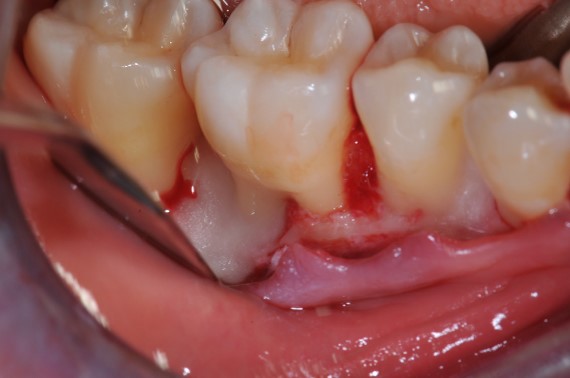

05/22 - Access flap (simplified papilla preservation technique between #44 and #45 and amplified papilla preservation technique between #47 and# 46). Buccal view.

Deep intrabony defects treated using Straumann® Emdogain® - Dr. M. Stefanini